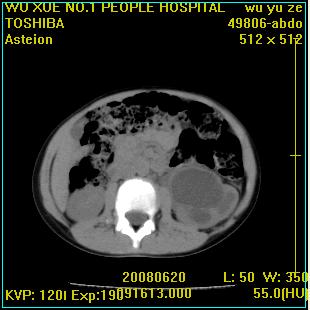

标题: PED0851:患儿,7岁,左腰部外伤一天,伴大量肉眼血尿。 [打印本页]

标题: PED0851:患儿,7岁,左腰部外伤一天,伴大量肉眼血尿。

左甚积液,输尿管近端扩张,考虑输尿管中下段梗阻

左输尿管上段梗阻伴左肾盂肾盏扩张积液

左肾积液,输尿管近端扩张,考虑输尿管中下段梗阻  ,左肾结核?

左肾积液,上段输尿管扩张。

左侧输尿管中段狭窄伴输尿管肾积水,考虑先天性狭窄可能性大.

左肾重度积水,原因不明;不排除左输尿管上段迷走血压迫或先天性狭窄所致可能。

左肾积水,输尿管上段扩张.考虑左输尿管下段狭窄受阻.

左肾积水,左侧输尿管上段扩张。

支持左肾积水,输尿管上段扩张.考虑左输尿管下段狭窄受阻

左肾重度积水

支持左肾积水,输尿管上段扩张.考虑左输尿管下段狭窄受阻。